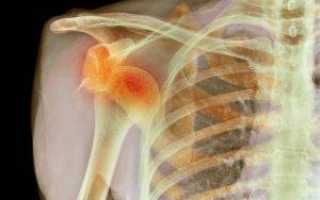

На этих фото показано, какие кости относятся к скелету пояса верхней конечности:

Основные движения в сочленении плеча выполняются при помощи головки, расположенной в глубине лопаточной кости. Плечевой сустав испытывает большие нагрузки. Из-за этого воспаление и структурный износ кости – явление достаточно частое. Для установления диагноза врач может направить на проведение рентгеновского исследования. Полученное при этом фото позволит максимально точно оценить состояние сустава.